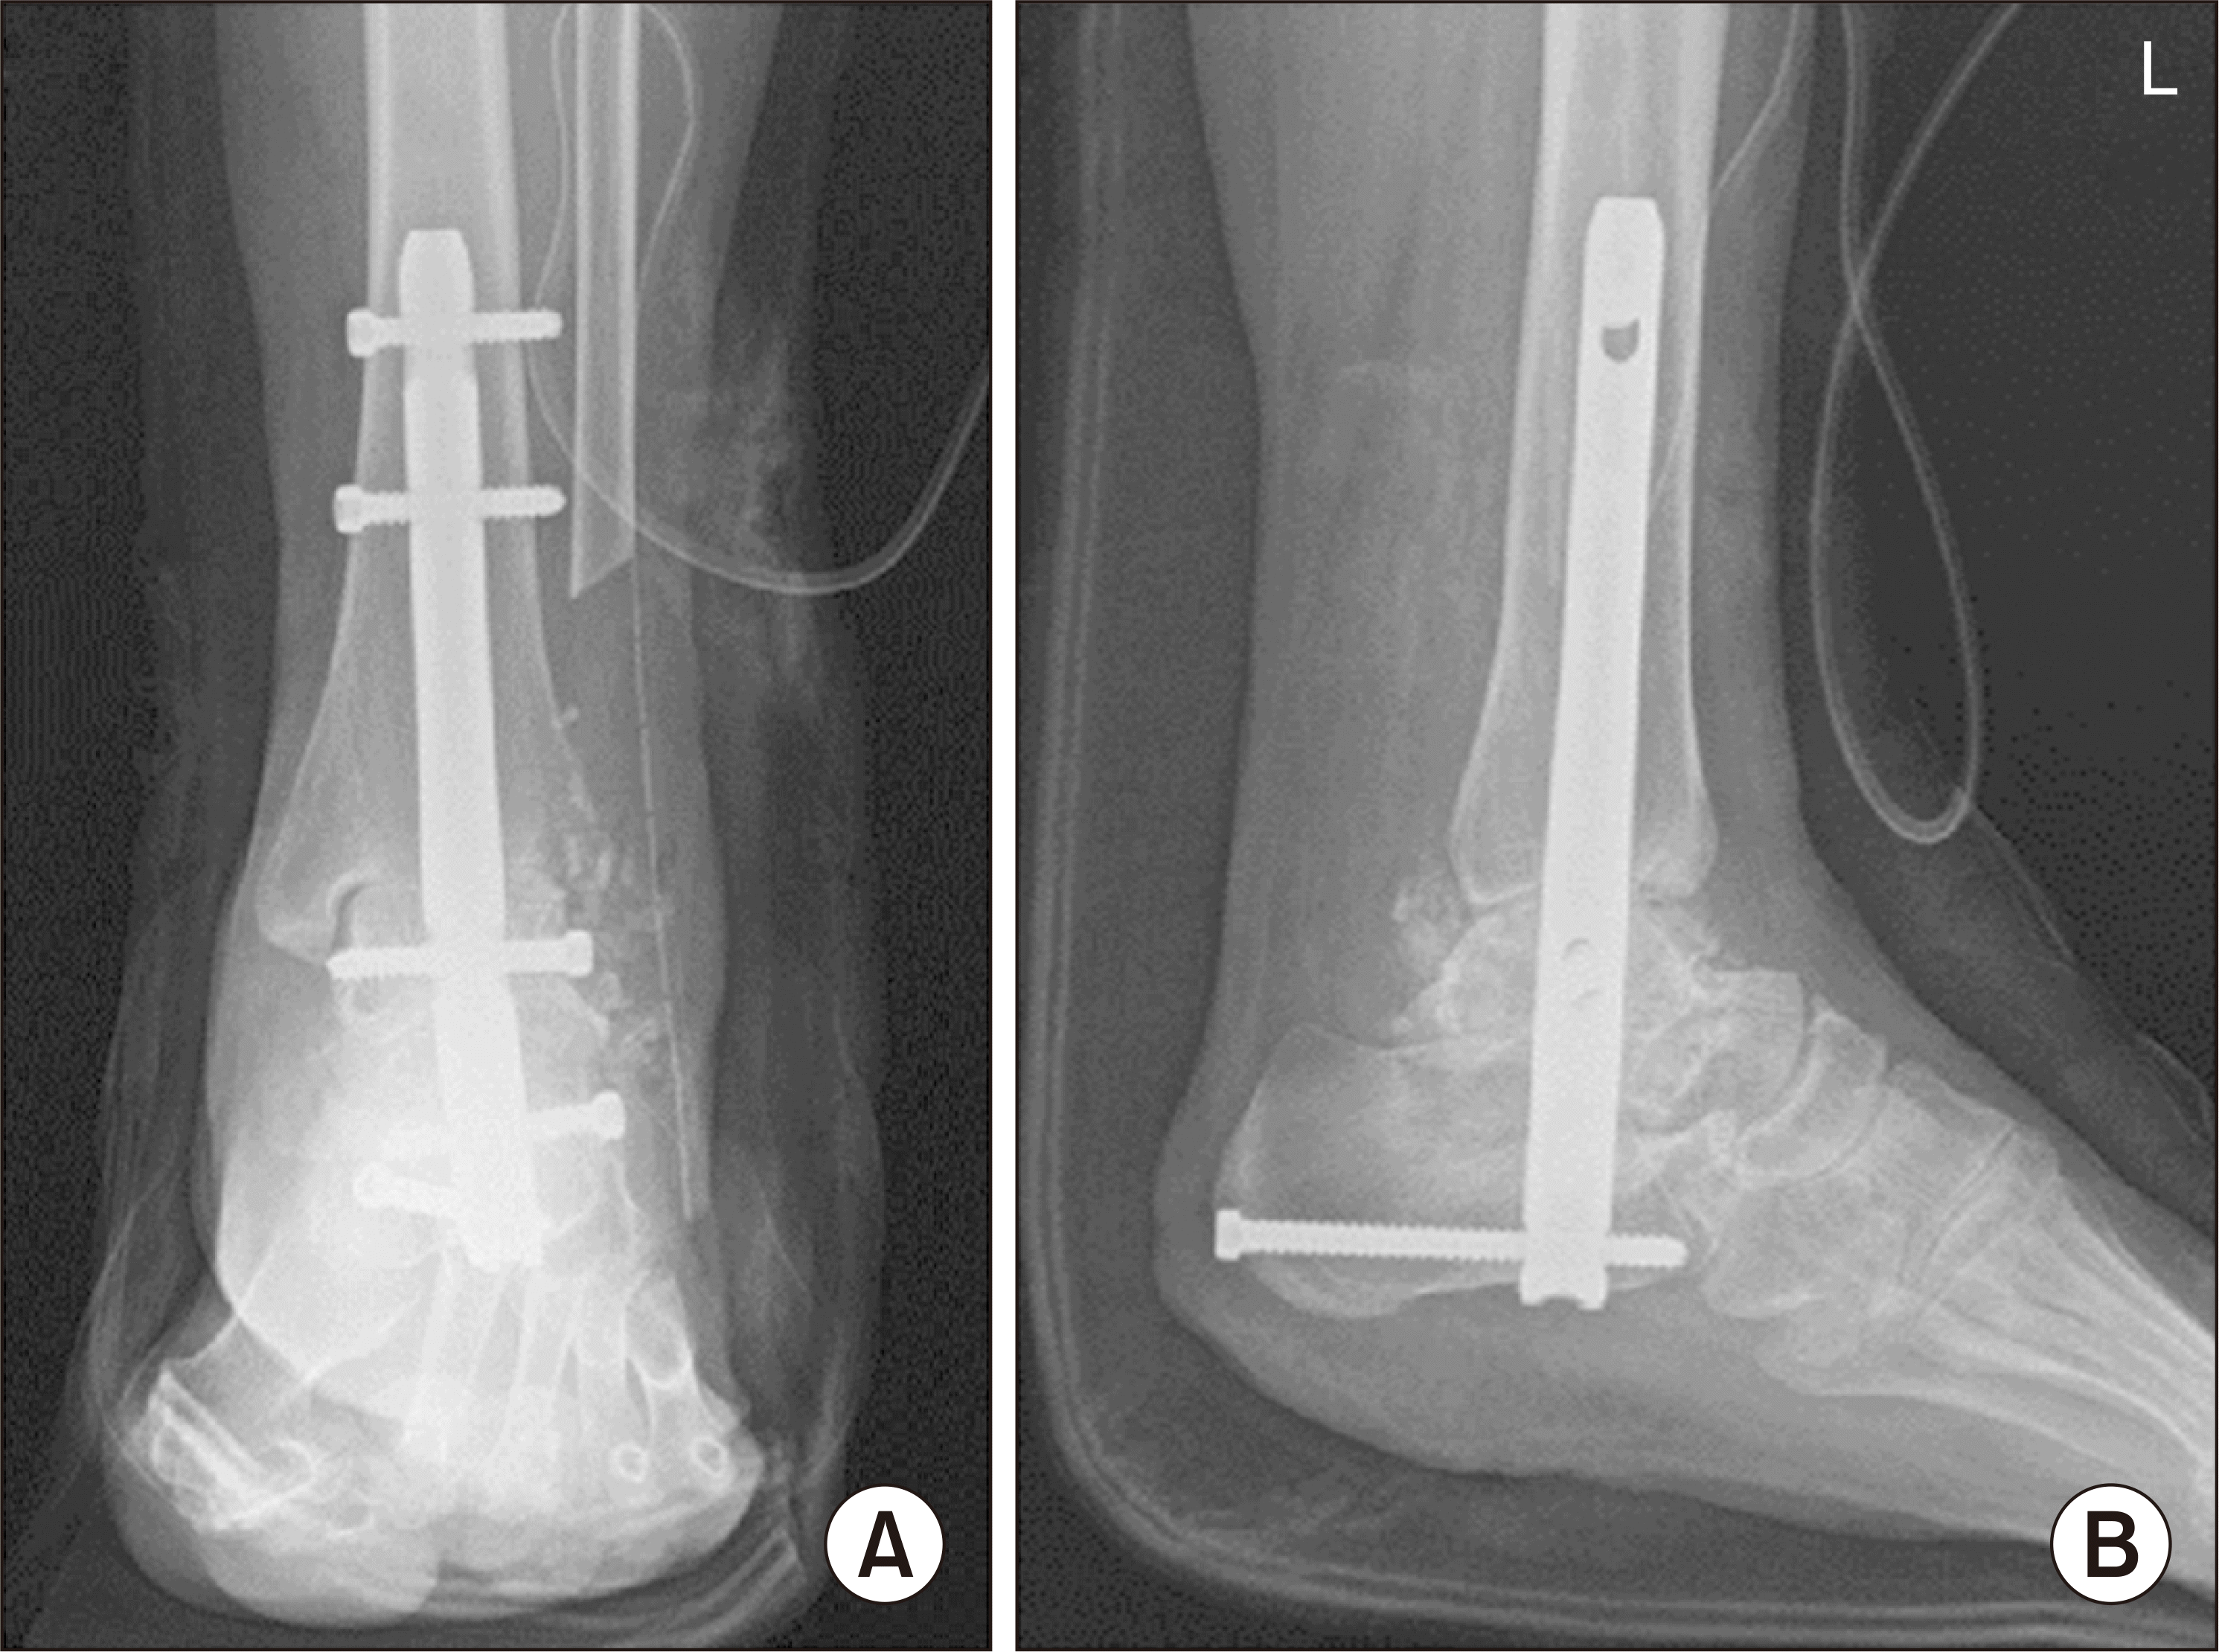

수술 1개월 전 한국공공조직은행(Korea Public Tissue Bank)으로부터 동종 거골을 주문하였다. 이전에 시행한 환자의 병변측 발목의 전산화 단층촬영(computed tomography, CT) 이미지를 사용하여 거골의 길이, 높이, 폭을 계측하였고 이를 토대로 환자 거골의 크기에 맞는 동종 거골을 주문하였다. 수술은 측와위에서 좌측 족관절의 비골 후방부터 족근동으로 이어지는 피부 절개를 시행하여 족관절 상방 5 cm 부위에서 비골 원위부 절제를 시행하였다. 수술 중 육안상 염증 소견은 관찰되지 않았다. 비골 원위부 절제 후 노출된 거골 체부와 경부, 종골의 일부 골괴사 병변을 확인 후 괴사 조직 절제를 시행하였다(Fig. 2). 이후 종골의 후방 관절면과 원위 경골 관절면의 남아 있는 연골을 큐렛과 절골도를 이용하여 연골하 골이 노출될 때까지 절제를 시행하고 다발성 천공술을 시행하였다. 미리 식염수에 담아 해동시켜 둔 동종 거골을 동일한 과정으로 관절면의 연골을 절제하고 다발성 천공술을 시행하였고(Fig. 3), 골결손 부위에 거골의 크기 및 관절 상합성이 잘 맞는지 확인 후 관절에 삽입하였다. 절제되었던 원위 비골 골편과 탈회 골기질(demineralized bone matrix) 이식 제재를 사용하여 경거관절 및 거골하 관절에 골이식을 시행하였다. 이후 족관절의 5도 외반, 5도 외회전을 유지한 상태에서 골수강내 금속정(Stryker T2 nail)을 삽입하였다(Fig. 4).

환자는 수술 후 1주째 특이 합병증 없이 퇴원하였고 수술일로부터 6주간 비체중부하 및 단하지 석고고정술을 시행하였다. 수술 중 시행한 연부조직 및 골조직의 세균 배양 검사는 음성으로 결과가 나왔다. 이후 추시 전기간 동안 감염, 임플란트로 인한 불편감 등의 합병증은 발생하지 않았다. 환자 수술 후 2년째 외래 추시에서 수술 전 8점이었던 visual analogue scale score가 1점으로 감소하였고 증상의 호전과 함께 radiograph에서 경거종골 관절의 유합이 확인되었다(Fig. 5). 2년 추시 radiograph에서 수술 직후 radiograph에 비하여 경거종골 관절의 5 mm 높이 소실이 관찰되었으나 환자는 이로 인한 불편감을 따로 호소하지 않았다.